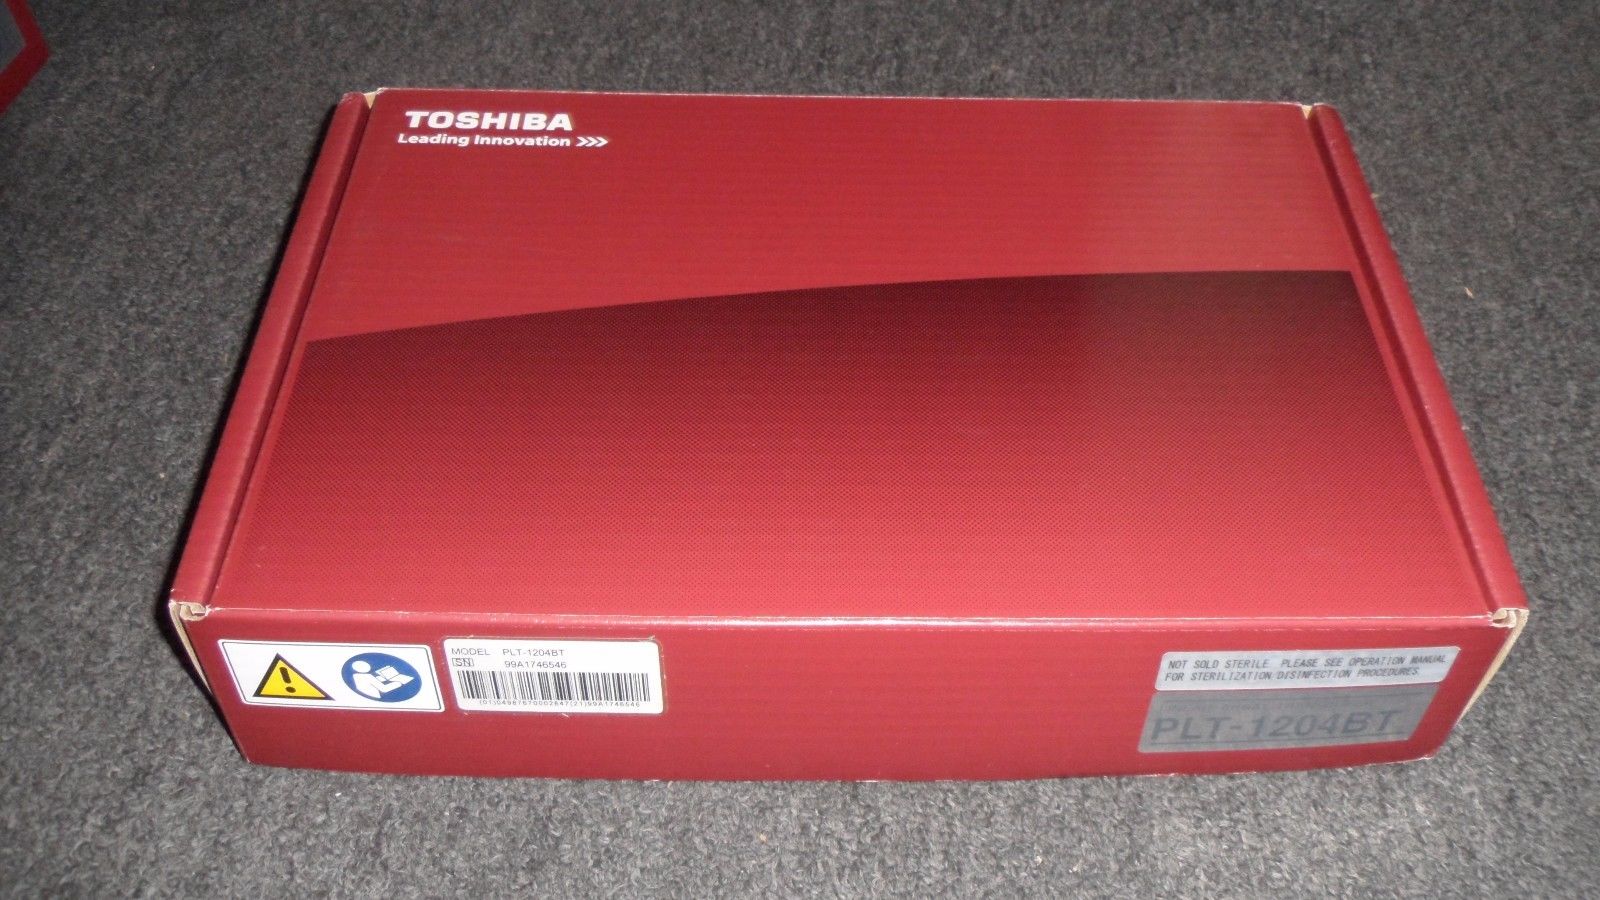

Toshiba Probes

DIAGNOSTIC ULTRASOUND MACHINES FOR SALE